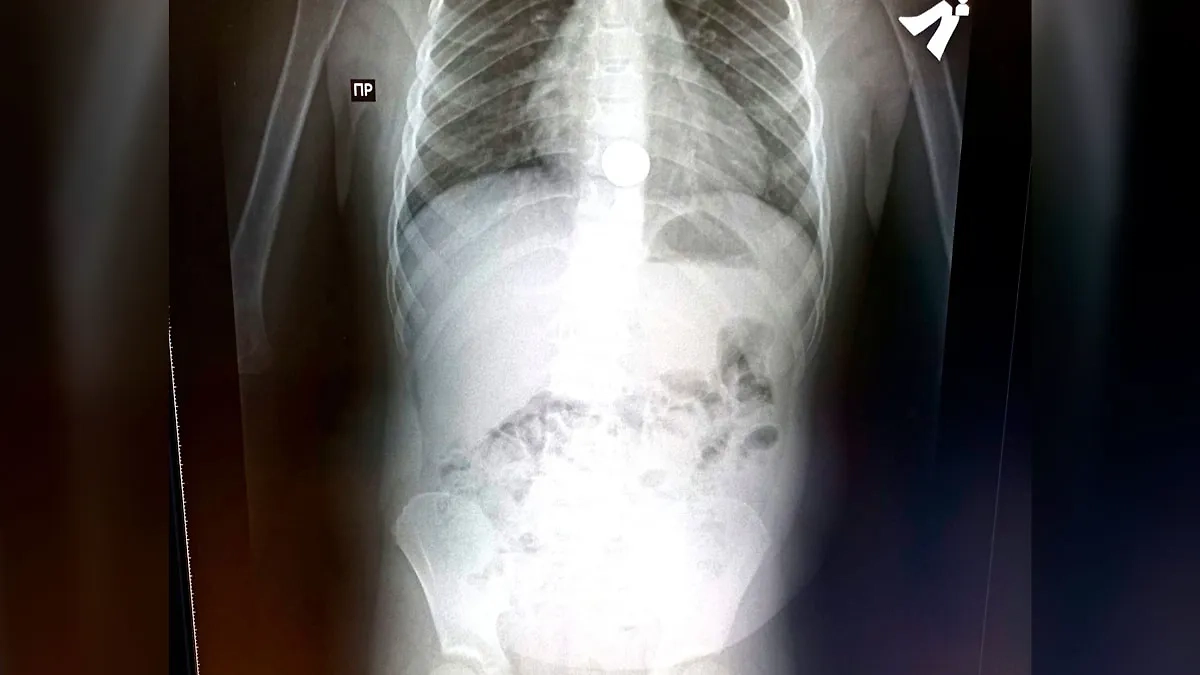

Рентгеновский снимок ребёнка, проглотившего монету в Башкирии. Фото © VK / Алик Янышев

Хирург Фаниль Валишин и эндоскопист Илюза Халикова экстренно провели рентген органов грудной клетки и брюшной полости и обнаружили проглоченную монету в проекции пищевода. Затем под общим обезболиванием медики извлекли инородный предмет. Мальчика выписали из больницы уже на следующий день.